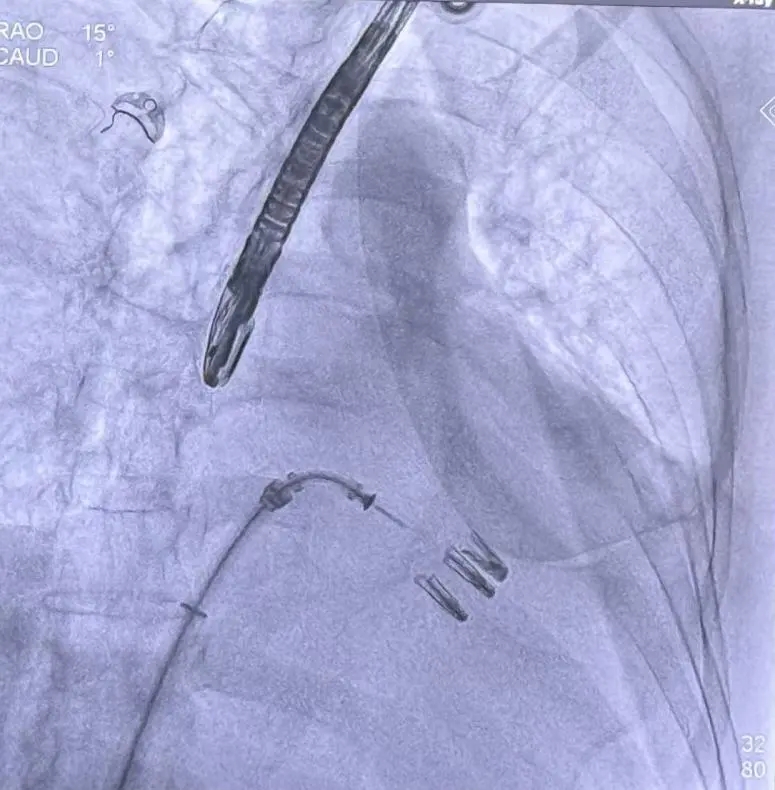

该例患者为DMR,脱垂区域较宽,术前制定手术策略:使用2把XTR先于患者外侧交界至1区部位进行钳夹。术中房间隔穿刺高度为4.0cm。成功穿刺后将SGC和XTR-CDS依次送入左心房,通过操控“M”旋钮调节SGC,使二尖瓣夹避开华法林脊,成功定位于2区正上方。在2区进行弹道测试成功后,进行Orientation调整。第一把于外侧交界区夹持,第二把于1区夹持,术中成功捕捞和夹持瓣叶后缓慢关紧夹臂,TEE检查见二尖瓣反流程度降低至1+,术后平均跨瓣压差3mmHg,手术顺利结束。

SCG进入左房

第二枚XTR定位